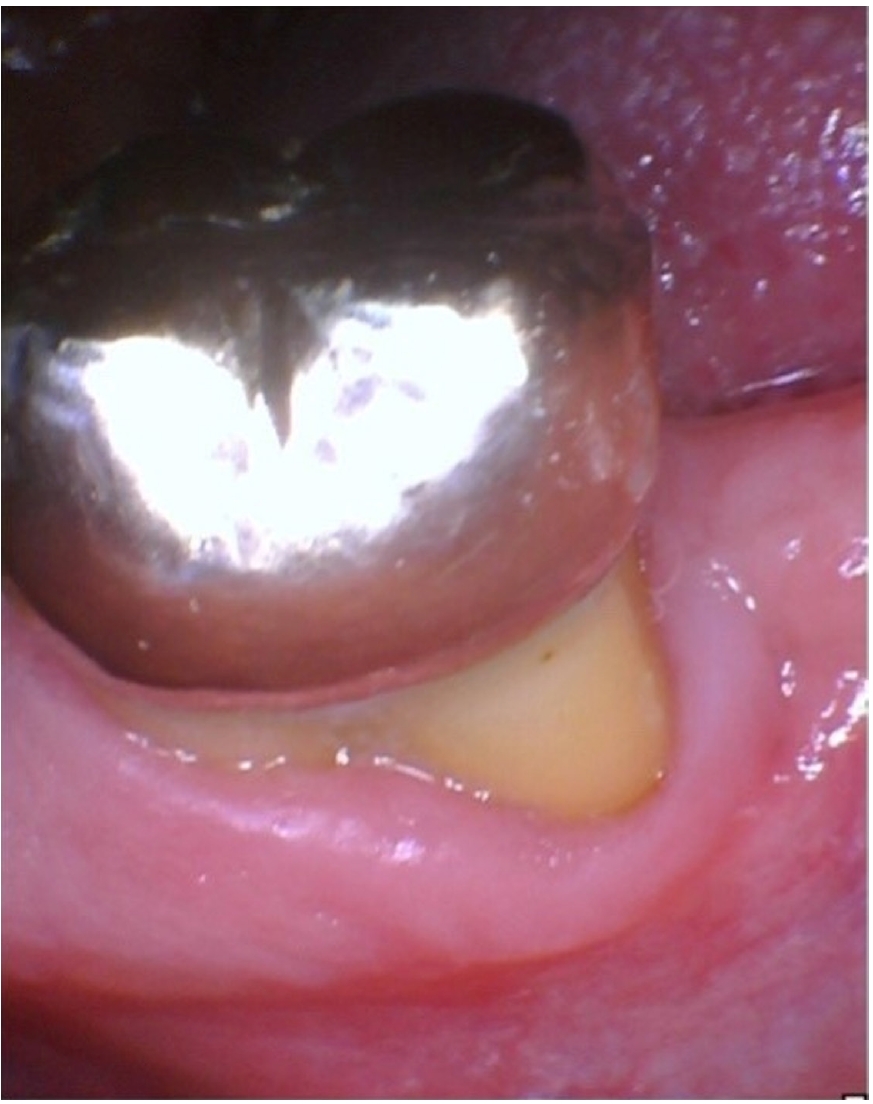

The patient was lost to follow-up until he reported again at 24 months, at which time clinical examination revealed that a full-coverage restoration on tooth #18 had been placed, restoring form and function (Figure 6). Clinical gingival health was noted on a reduced periodontium. Draining sinus tract remained resolved, and probing depths were improved to 3–4 mm. The tooth exhibited no mobility. Periapical radiograph (Figure 7) showed significant resolution of the periapical radiolucency with substantial bone regeneration along the length of the distal root. The patient was greatly appreciative that his natural dentition was conserved, which motivated him to ensure continued dental care maintenance.

Figure 6.

Twenty-four-month recall showing that the tooth has been restored with an extracoronal restoration and absence of draining sinus tract. Gingival health on a reduced periodontium is noted.

rde-2025-50-e31f6.jpg

Figure 6. Twenty-four-month recall showing that the tooth has been restored with an extracoronal restoration and absence of draining sinus tract. Gingival health on a reduced periodontium is noted.